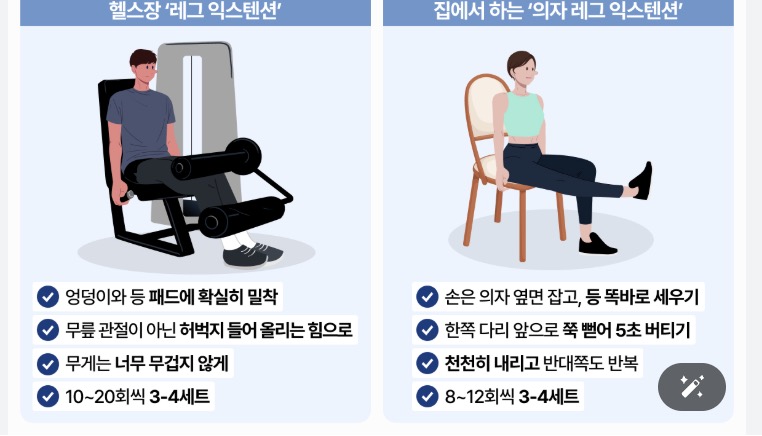

추운 겨울철에도 실내에서 안전하게 할 수 있는 관절 운동을 소개합니다:

- 앉았다 일어나기 운동 (하루 10회씩 3세트)

- 다리 들어올리기 (각 다리 15초씩 유지)

- 무릎 굽혔다 펴기 (20회씩 3세트)